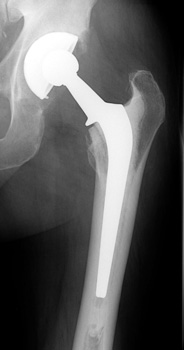

Total Hip Arthroplasty

• Used in patients with arthritic conditions that involve the acetabulum and the femoral head

• Types

• Non cemented

• Porous coated

• Press fit

• Hybrid (only femoral component cemented)

• Cemented

Non Cemented

Hybrid (only femoral component cemented)

Cemented